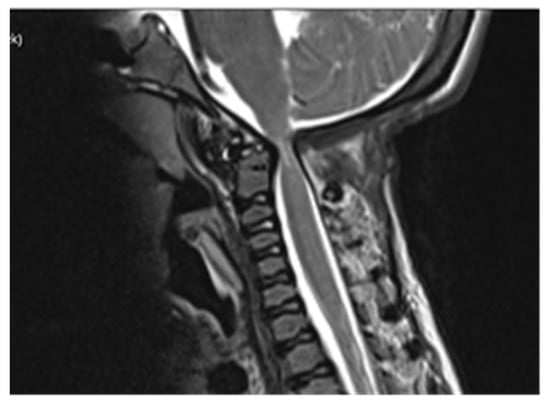

Computed tomography (CT) scan of cranio-cervical junction revealed bifid arch of the atlas as a part of skeletal disorders. Additional preoperative magnetic resonance imaging (MRI) revealed a critical stenosis of cranio-cervical junction with concomitant myelopathy (Figure 3).

Follow-up MRI scan of cranio-cervical junction after three months and one year revealed residual stenosis of CCJ and myelopathy of cervical medulla. Nevertheless, the postoperative diameter of decompressed CCJ was insignificantly wider in the sagittal and axial planes compared to preoperative MRI scan (Figure 5).

A preoperative magnetic resonance imaging (MRI) scan revealed a severe myelopathy at the level of cranio-cervical junction and radiologic signs of atlanto-axial instability. Therefore, the authors decided to obtain only bone decompression of the foramen magnum and C1 vertebra to prevent any possible neurological deterioration with the aim of achieving a better radiologic outcome, e.g., partial or nearly complete regression of myelopathy. There were no radiological signs of platybasia and basilar invagination according to radiographic measurements of cranio-cervical junction.

Despite an adequate decompression of the CCJ, a postoperative follow-up MRI scan revealed only a limited widening of the diameter of the cranio-cervical junction caused by radiologically confirmed atlanto-axial instability. There was no sign of regression of myelopathy. The authors did not confirm the utmost benefit of surgery according to radiological follow-up.

Figure 3. Preoperative MRI scanning of cranio-cervical junction revealed critical stenosis and myelopathy, 14 years of age.

Figure 5. Postoperative MRI revealed insignificant radiological differences comparing to preoperative scanning with persistent myelopathy (15 years of age).